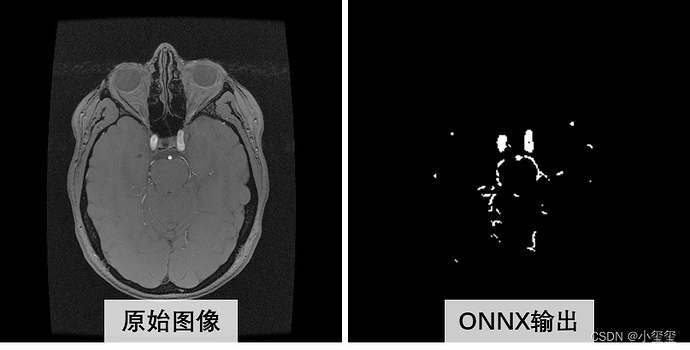

从下图可以看出,量化ONNX的推理结果和原始ONNX推理结果,主体上是相似的,局部有细微的差异(量化必然存在或多或少的精度损失,大部分情况下是可用的)。

其实我最开始以为onnx的输入preprocess_calibration,运行时候报错,错误信息说维度应该是[1,256,256,3],然后我回去看onnx结构才发现预处理节点名叫HzSQuantizedPreprocess,剩余的两个onnx节点名是HzPreprocess。